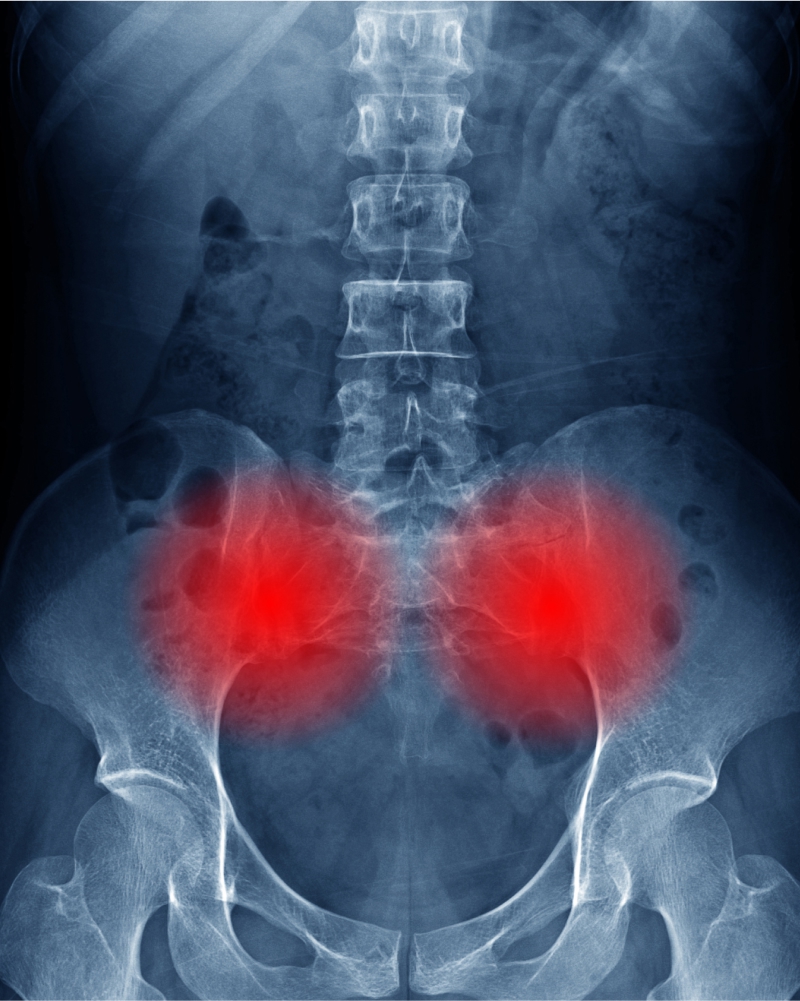

- Significant aggravation of his pre-existing hip arthritis

Over the coming months, Manuel needed a number of medical procedures to help him manage his back pain, hip pain, and other symptoms. He tried a series of steroid injections in his back and hips, but each injection brought only partial and temporary relief.

Without any other options, Manuel needed total joint replacement surgeries on both of his hips. And after the left hip surgery, he experienced an infection that complicated his recovery. His physician also told Manuel that he would probably need a spinal surgery in the future.